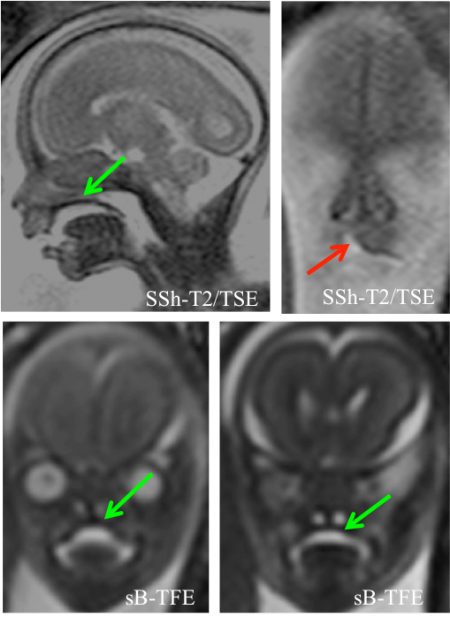

Pokud je vysloveno podezření na výskyt obličejového rozštěpu, zpravidla je těhotná žena odeslána na ultrazvukové vyšetření do specializovaného centra. Zde je opět nejprve provedeno klasické dvojrozměrné (2D) ultrazvukové vyšetření. Ideální je navíc připojení troj- a čtyřrozměrného (3D/4D) ultrazvukového vyšetření, které zprostředkuje lepší informaci o oblasti patra plodu (obrázek č. 4). Navíc napomůže 3D/4D ultrazvukové zobrazení rodičům pochopit rozsah vady a o její vliv na vzhled obličeje jejich budoucího miminka (obrázek č. 5). Dalšího zpřesnění diagnostiky rozštěpové vady je možné dosáhnout rozšířením vyšetření o zobrazení magnetickou rezonancí (obrázek č. 6). Tato metoda se často provádí při podezření na výskyt rozštěpu u plodu nebo při nejasném nálezu při základním ultrazvukovém vyšetření u těhotné ženy, která je v úzkém příbuzenském vztahu s jedincem postiženým rozštěpem (matka či otec plodu, starší sourozenec plodu a podobně).

Obrázek č. 6.: Vyšetření magnetickou rezonancí u plodu s malým jednostranným rozštěpem rtu. Červená šipka směřuje k rozštěpu rtu, zelené šipky ukazují na intaktní ploténku patra plodu.

(Foto: MUDr. Veronika Frisová, Profema)